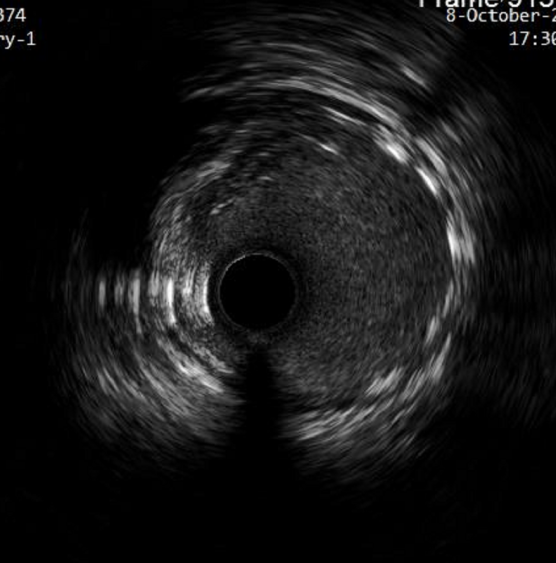

手术过程中,由周玉杰教授团队在操作端操作控制,ETcath血管介入机器人在手术室精确地实施了对患者的PCI手术。冠状动脉造影显示LAD近段重度狭窄,同时通过介入机器人成功推送导丝到达前降支远段 然后使用IVUS超声导管检查,证实血管狭窄程度较重。

术后超声